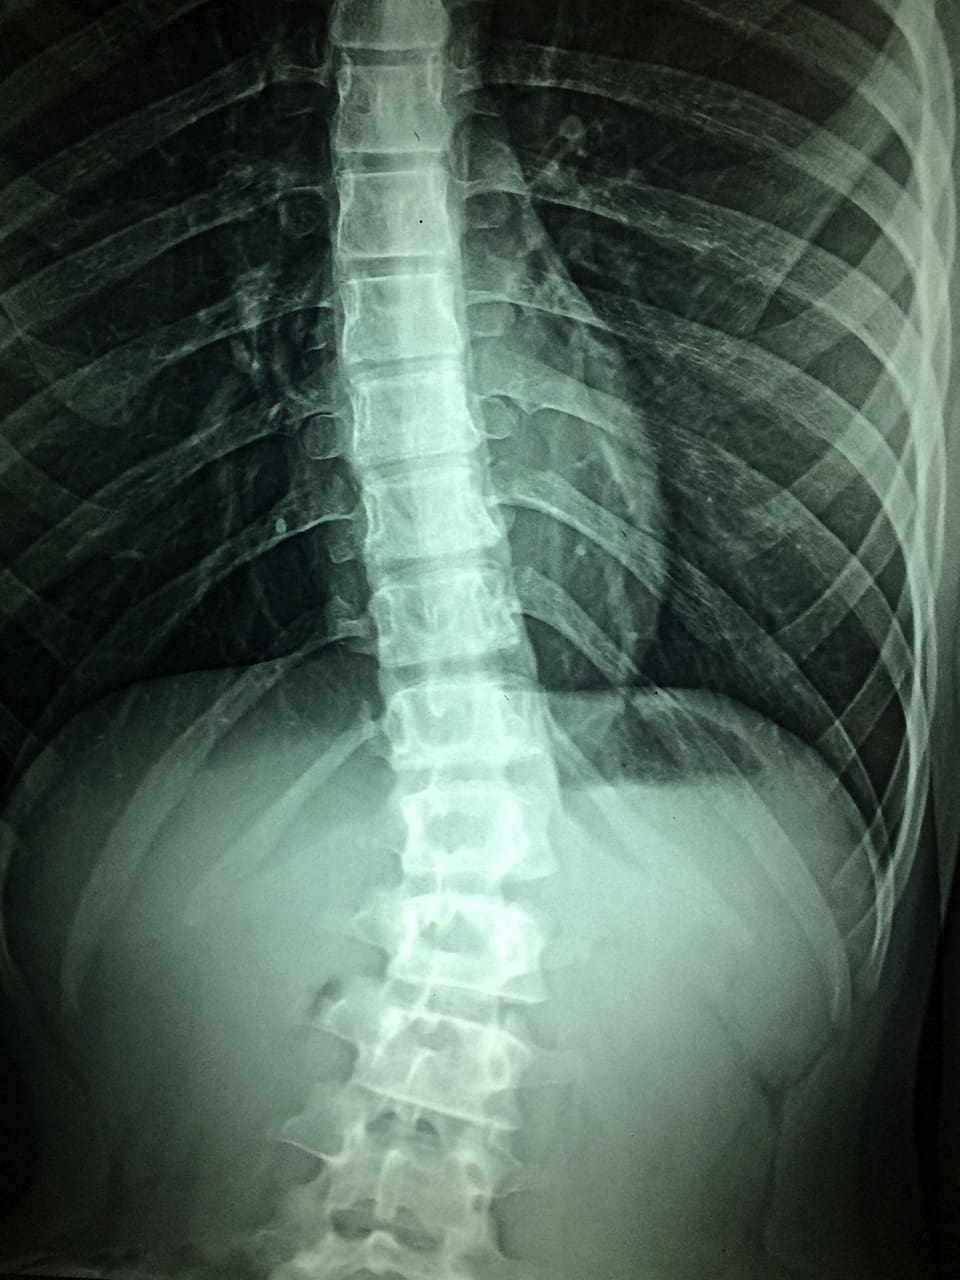

Diagnosis of Spinal Instability

Diagnosing spinal instability requires a comprehensive evaluation that may include:

- Physical Examination: Your healthcare provider will assess your range of motion, strength, and reflexes to determine any signs of instability.

- Imaging Studies: X-rays, MRI, or CT scans may be used to visualize the spine’s structures and identify any abnormalities.

- Dynamic Testing: Specialized tests like flexion-extension X-rays can assess the spine’s stability under different positions.